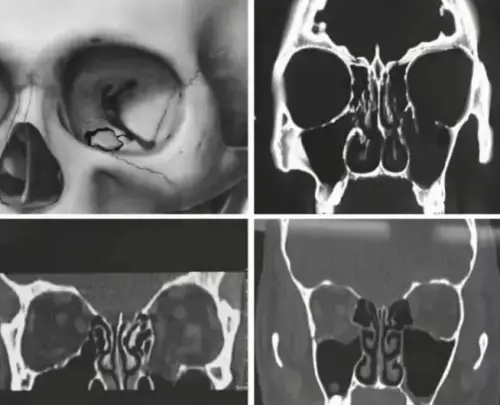

Titanium alloy is non-magnetic and has little effect on CT and MRI scans, ensuring high-quality imaging. After orbital fracture repair surgery, patients require frequent follow-up examinations to monitor their recovery. Using titanium alloy as a repair material does not interfere with imaging findings, allowing doctors to clearly observe the healing of the fracture site and the condition of the implant. Titanium Home emphasized in a follow-up report that this advantage provides a crucial basis for postoperative diagnosis and treatment, helping to promptly identify and address potential problems.

Since its first successful application in orbital repair in 1990, titanium mesh has been widely used as a filling and internal fixation material for the repair of orbital wall and floor defects. However, it also presents some significant challenges.